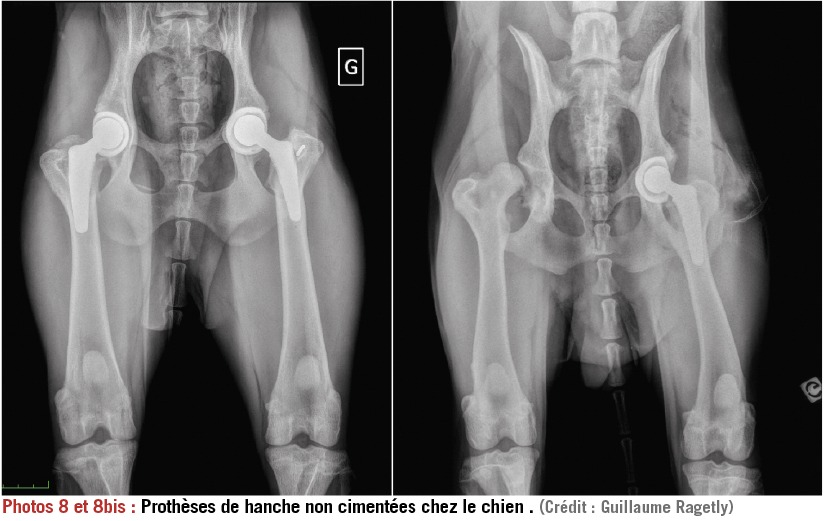

La chirurgie

Dans certains cas, la chirurgie constitue une solution palliative quand la douleur et l’arthrose sont trop importantes pour être gérer médicalement. Ainsi, une prothèse totale de hanche uni ou bilatérale peut être envisagée pour soulager une sévère arthrose coxo-fémorale avec un taux de réussite de 90% dans la reprise d’une activité normale si l’animal est ramené à un poids de forme. Les autres chirurgies palliatives les plus courantes sont les prothèses de genou ou les arthrodèses qui consistent à « fixer » une articulation devenue trop douloureuse. Le principal frein à cette solution est le coût très élevé de ces interventions spécialisées.

Prothèses totales de hanches.

copyright Dr Ragetly CHV frégis